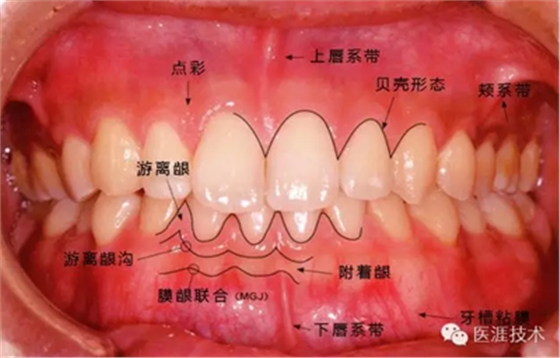

①健康、正常的牙周組織如何形成?

健康牙周組織的牙齦邊緣呈珊瑚粉,邊緣牙齦略呈圓弧狀。牙間可見(jiàn)三角形的牙間乳頭,牙齦邊緣相連呈貝殼形。

附著齦與游離齦相連時(shí),有時(shí)有游離齦溝存在(成人的30~40%)。

附著齦通過(guò)膠原纖維牢固結(jié)合骨骼與牙骨質(zhì),因此可見(jiàn)不可動(dòng)、硬而緊繃的點(diǎn)彩(橘皮樣點(diǎn)狀凹凸)。

從牙齦牙槽粘膜到根尖有牙槽粘膜。牙槽粘膜為暗紅色,與骨骼結(jié)合較松,故可動(dòng)。

健康且正常的牙周組織臨床圖像